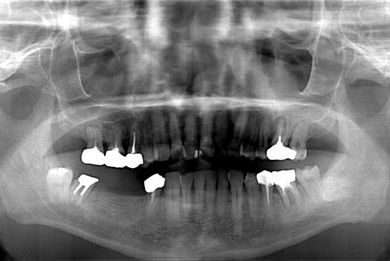

インプラント治療+セラミック治療

| 性別/年齢 | 男性 / 58歳 | ||||||||||||||||||||||||||||||||

| 主訴 | 部分入れ歯のバーが舌に当たるため、奥歯2本のインプラント治療を希望。 | ||||||||||||||||||||||||||||||||

| 治療方針 | 右下欠損部分をインプラント治療にて、機能的・審美的回復を行う。 | ||||||||||||||||||||||||||||||||

| 治療内容 | インプラント2本、メタルボンドセラミッククラウン8本、メタルボンドセラミック用土台6本 | ||||||||||||||||||||||||||||||||

| 総治療費 | 1,474,620円 | ||||||||||||||||||||||||||||||||

| 治療期間 | 1年6ヶ月 |